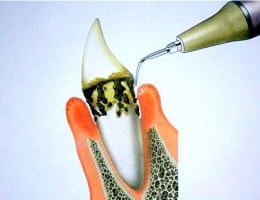

超音波スケーラー

超音波スケーラーは、主に歯肉縁上歯石のスケーリングを行なう際に使用します。

超音波スケーラーは、毎秒約25000~40000回の振動によって歯石を破壊し、除去します。

また、超音波スケーラーは歯石の除去以外にも、クラウンなどの補綴物の除去や根管洗浄にも使用されることがあります。